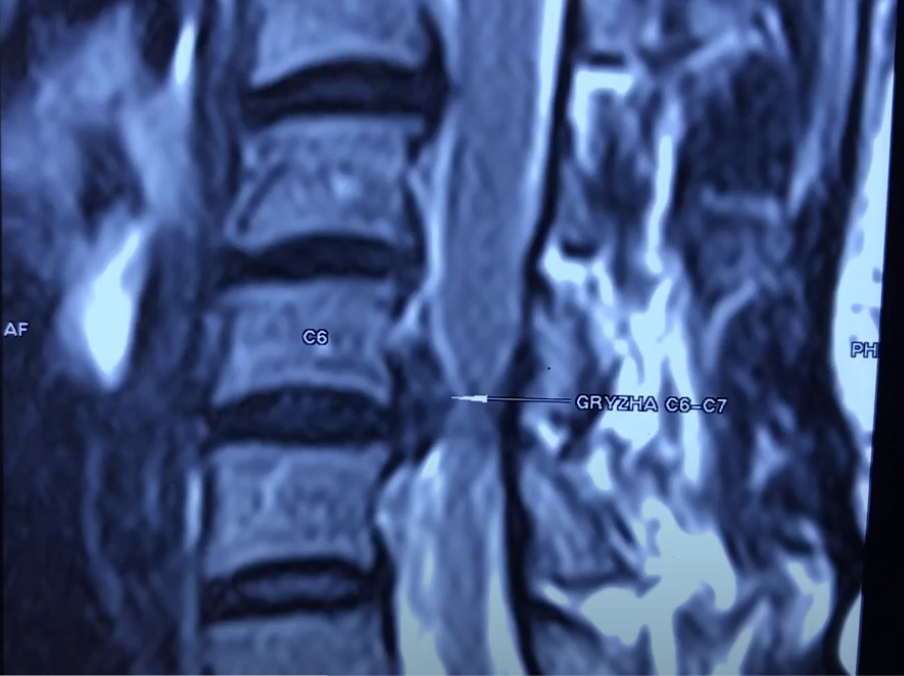

Пациентка обратилась в клинику с жалобой на резкие, нестерпимые боли в руке. Выполнив МРТ, обнаружили большую грыжу на уровне C6, C7. Такая грыжа чаще возникает в поясничном отделе, но у девушки образовалась в шейном отделе позвоночника.